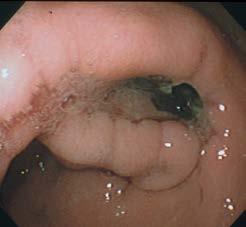

The skin and subcutaneous tissues were erythematous and extensively thickened over the ventral abdomen bilaterally, extending down both hindlimbs to the stifle region and cranially to caudal thorax. The thickening consisted of coalescing nodules with areas of ulceration and draining sinus tracts, as shown in the image of the ventral skin ( Figure 1).

Fine needle aspirates (FNA) were obtained from two subcutaneous nodules and impression smears from the ulcerated surfaces and stained with rapid Romanowsky stain (Rapid Diff, Australian Biostain). Image of the cytology smear is shown in Figure 2.

The smears are moderately cellular containing inflammatory cells and abundant round yeast organisms with occasional clusters of paired cocci bacteria in a light blue stippled proteinaceous background. The

Figure 1. Image of ventral abdominal skin lesions Figure 2. FNA from subcutaneous nodule (500x magnification)inflammatory cells are a mix of degenerate neutrophils, small lymphocytes and macrophages. Macrophages frequently contain yeasts and occasional neutrophils contain bacteria. The yeast are 5-15µm diameter with a thin pink cell wall and prominent unstained capsule (1-2µm diameter) and show rare narrow based budding.

Fungal and bacterial neutrophilic and histiocytic panniculitis/pansteatitis. Fungal morphology consistent with Cryptococcus species.

The clinical findings and cytology support cutaneous Cryptococcosis with secondary bacterial infection.